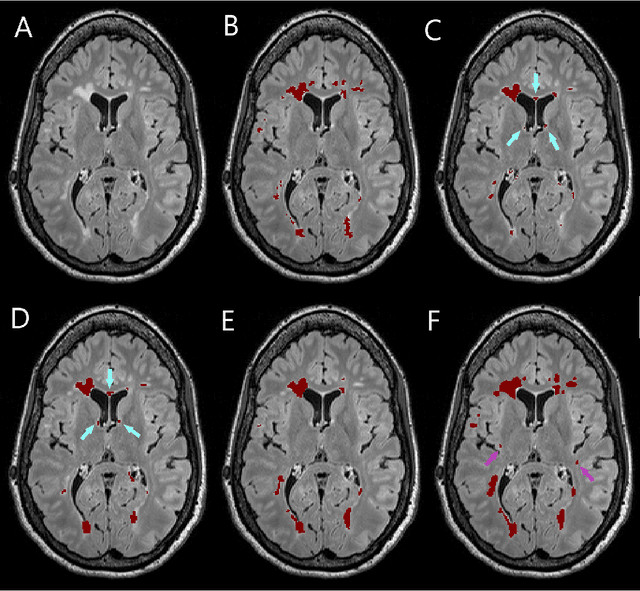

Abstract:Segmentation of both white matter lesions and deep grey matter structures is an important task in the quantification of magnetic resonance imaging in multiple sclerosis. Typically these tasks are performed separately: in this paper we present a single CNN-based segmentation solution for providing fast, reliable segmentations of multimodal MR imagies into lesion classes and healthy-appearing grey- and white-matter structures. We show substantial, statistically significant improvements in both Dice coefficient and in lesion-wise specificity and sensitivity, compared to previous approaches, and agreement with individual human raters in the range of human inter-rater variability. The method is trained on data gathered from a single centre: nonetheless, it performs well on data from centres, scanners and field-strengths not represented in the training dataset. A retrospective study found that the classifier successfully identified lesions missed by the human raters. Lesion labels were provided by human raters, while weak labels for other brain structures (including CSF, cortical grey matter, cortical white matter, cerebellum, amygdala, hippocampus, subcortical GM structures and choroid plexus) were provided by Freesurfer 5.3. The segmentations of these structures compared well, not only with Freesurfer 5.3, but also with FSL-First and Freesurfer 6.1.